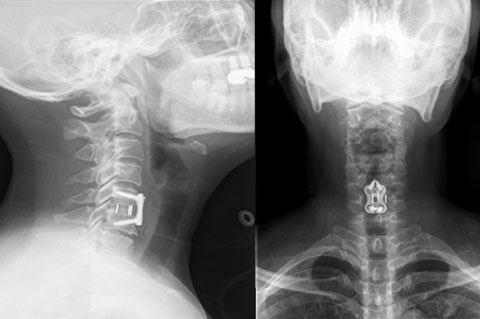

据悉,52岁的患者张女士因长期颈肩疼痛伴下肢无力、行走不稳,确诊为“颈椎间盘突出(C6-7节段)伴脊髓压迫”,既往因颈椎病行前路椎间融合(C5-6节段)后伴有颈椎活动受限,邻近节段退变加重进而出现症状。传统颈椎融合术虽能解除压迫,但会导致手术节段活动受限,且可能加速相邻节段退变。考虑到患者希望保留颈椎活动功能、尽快回归工作,李强主任牵头组织多学科讨论,最终确定采用“颈椎间盘置换术”这一先进术式。

术前正侧位X线

手术中,团队在显微镜下精准操作,仅通过100px的微创切口,成功摘除病变椎间盘,并植入适配的人工颈椎间盘假体。术后即刻解除神经压迫。术后第1天,患者颈肩疼痛、下肢无力状明显缓解;术后第2天顺利下床活动,经影像学检查确认假体位置精准、稳定性良好,目前已康复出院。

术后正侧位X线